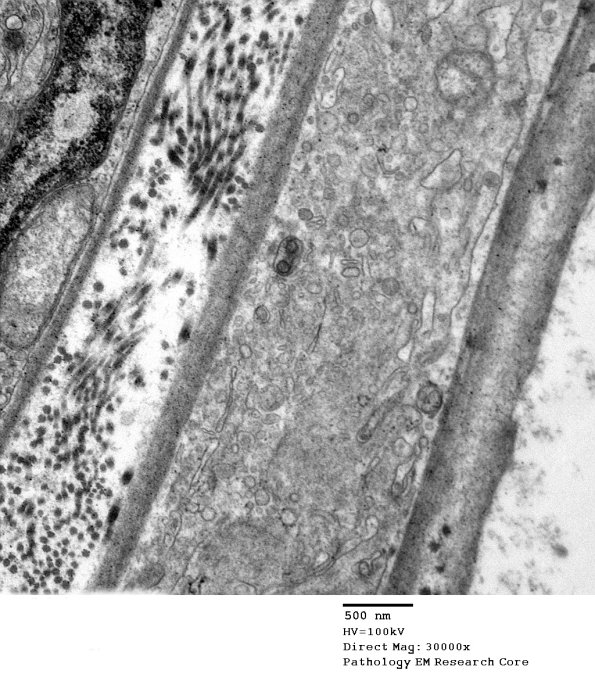

Other areas showed accumulation of intracellular organelles which suggest macrophage processes; however, the lack of autophagic vacuoles suggest they may belong to hyperplastic perineurial processes. (electron micrographs)